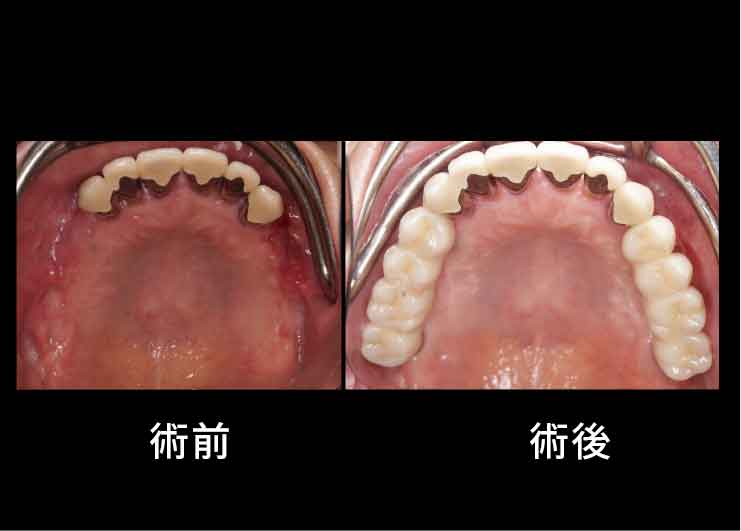

Case3. 65歳女性

歯周病でインプラント、歯が脱離。

上あごの骨が非常に薄く、そのままではインプラントを埋め込むことができないため、Xマークを使用したザイゴマ(頬骨)インプラントおよびプテリゴイド(蝶形骨)インプラントを行ったケース。

インプラントでかみ合わせをしっかりと回復したことで、もともとあったほうれい線が術後には消えました。

奥歯でしっかりと噛めるようになることで飲み込む力が改善し、咳き込むことを防げるようになるほか、このように見た目も若々しくなっていきます。

奥歯でしっかりと噛めるようになることで飲み込む力が改善し、咳き込むことを防げるようになるほか、このように見た目も若々しくなっていきます。